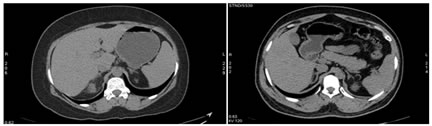

Figure 1: Manual tracing of adrenal gland volume

2a:                                                    2b

Figure 2- 2a: NCCT - Axial section showing Y shaped left adrenal gland; 2b: NCCT – Axial section, showing linear right adrenal gland and triangular left adrenal gland